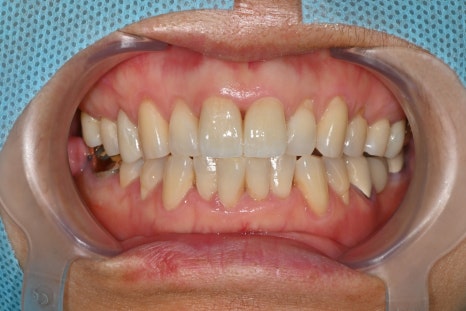

앞니 크라운 치료시행

충격을 크게 받은 앞니는 파절선이 생기거나 색이 변하고, 형태가 변형되기도 합니다.

환자분은 외상 이후 치아 모양과 기능이 변해

지르코니아 크라운으로 마무리 치료를 진행했습니다.

최종 크라운 장착 후 환자분은

예전처럼 자연스럽게 웃을 수 있어 좋다

입술 흉터도 깔끔하게 잘 아물었다

고 말씀해 주셨습니다.